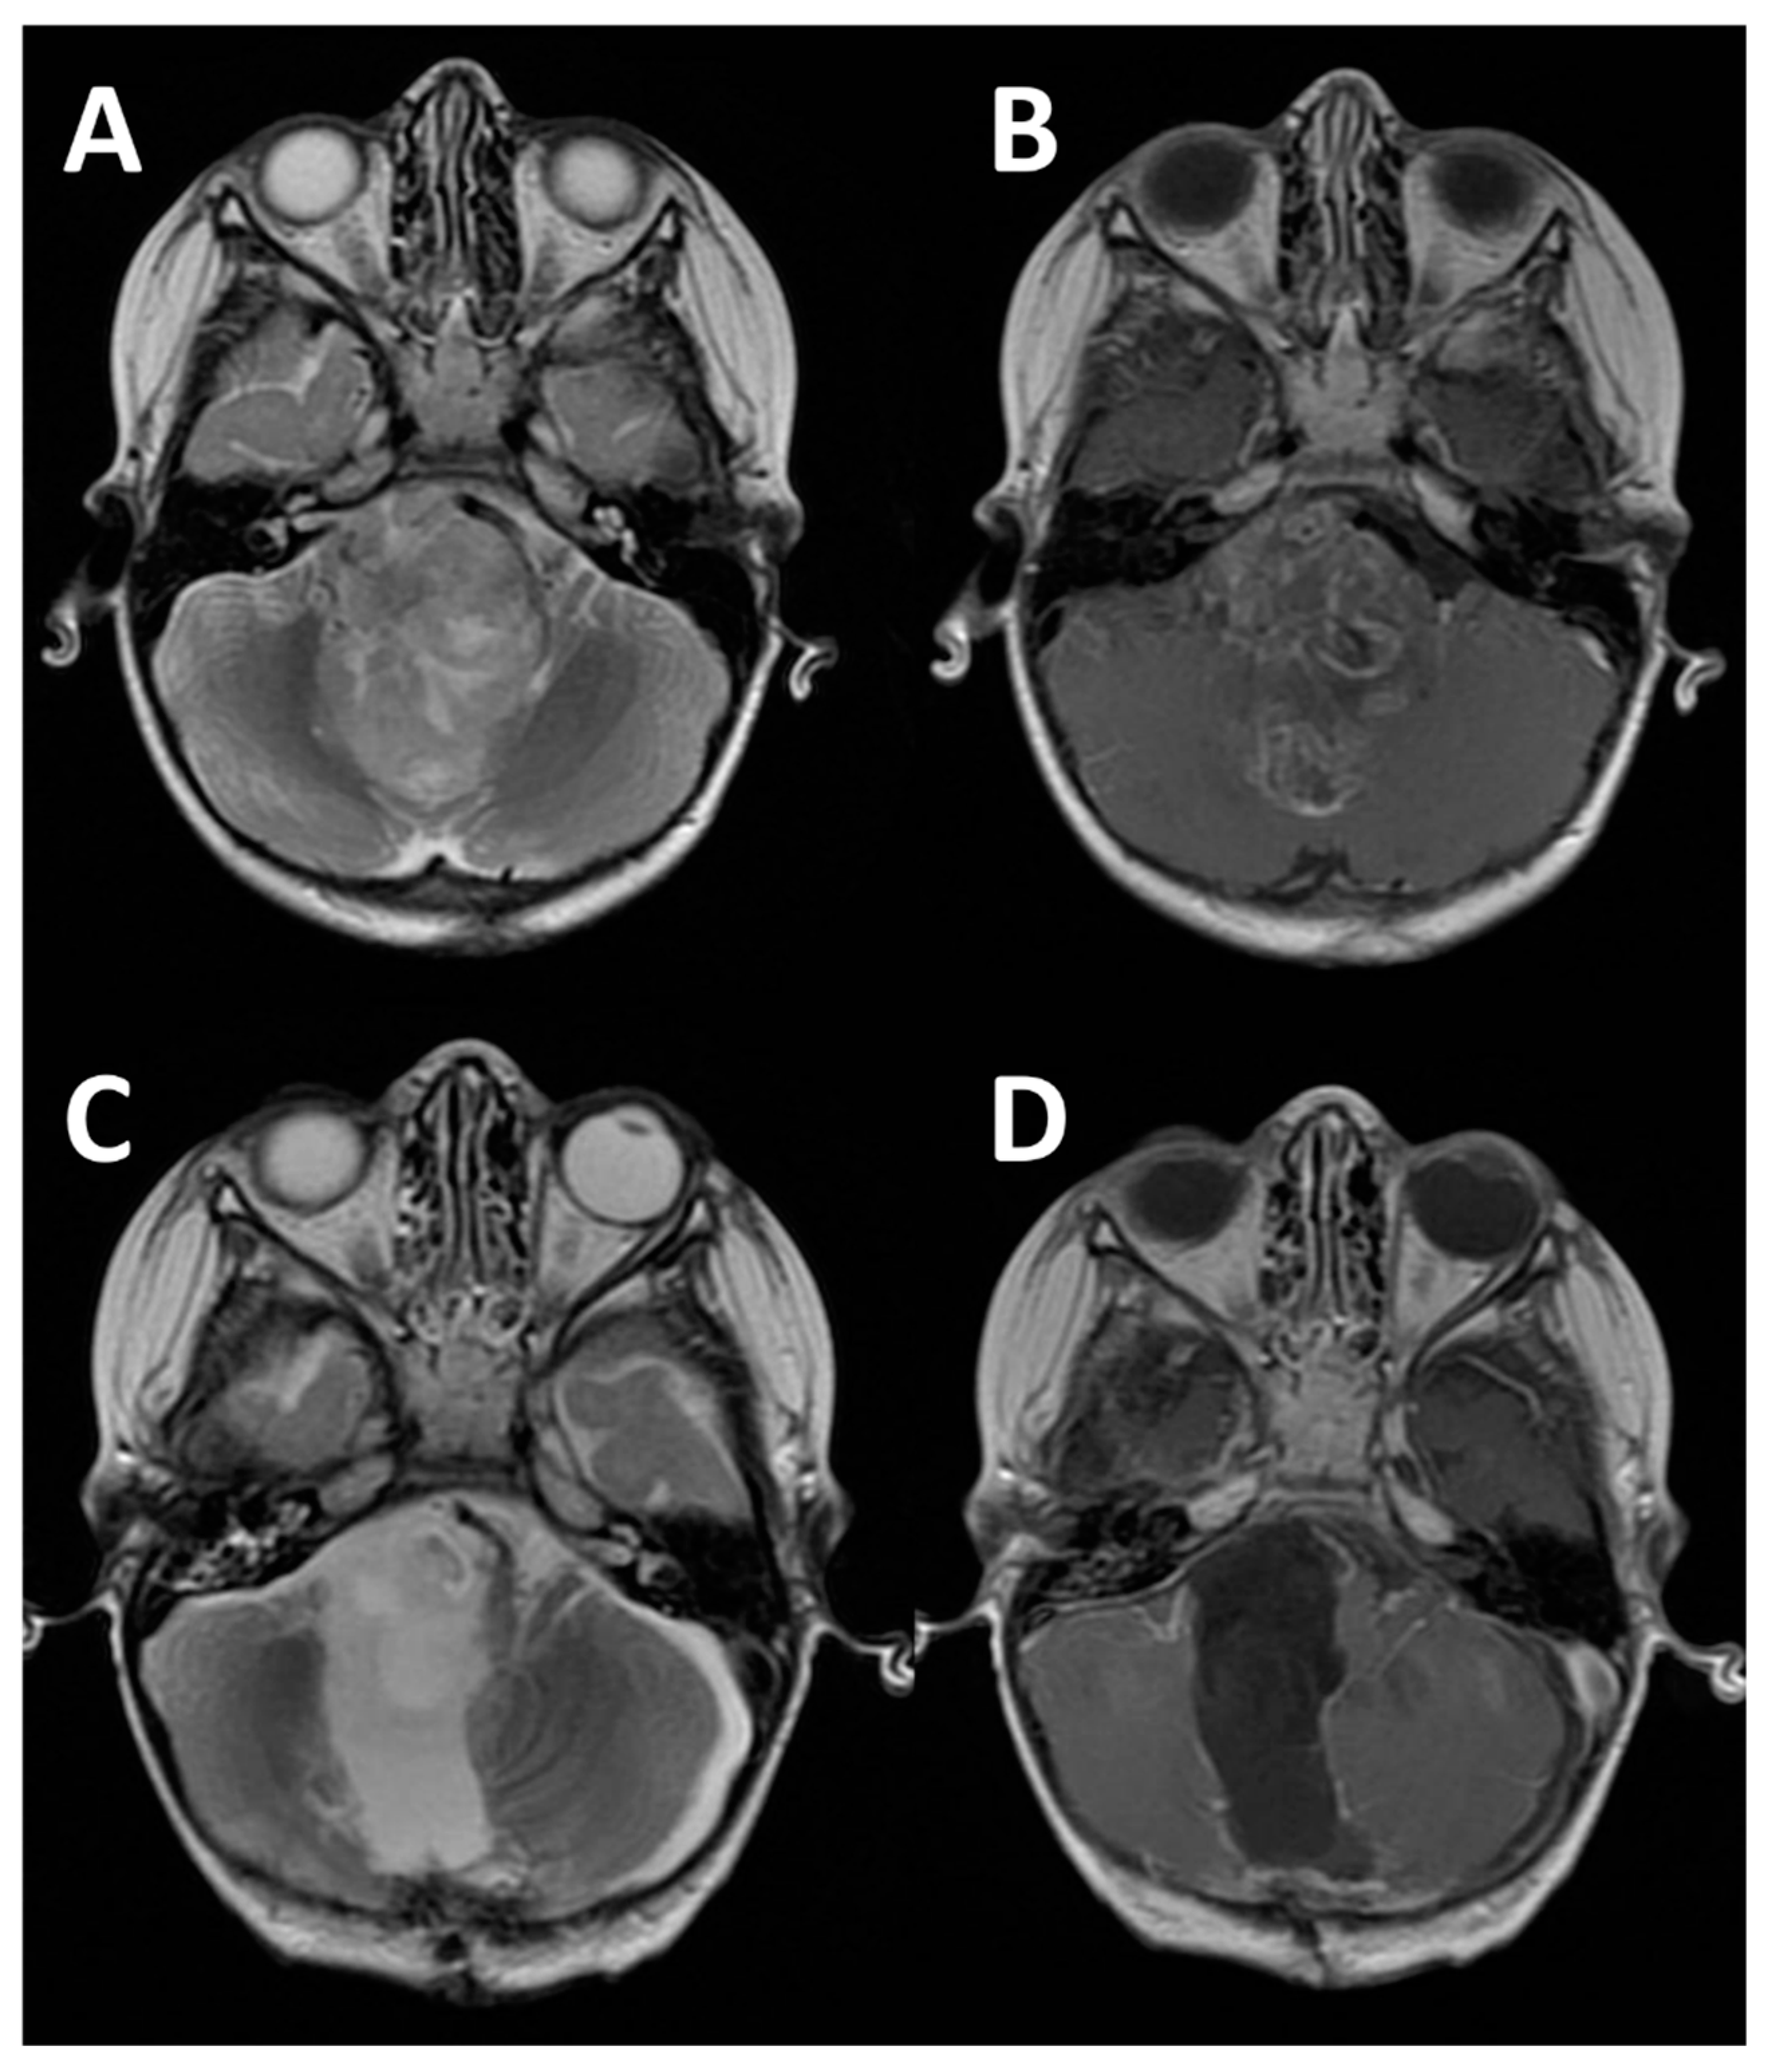

Figure 1. Example of tumor arising directly form the CPA. (A) Axial gadolinium MRI showing a bilateral CPA schwannoma in a 14-year-old girl with NF-2. In the box, IUOS demonstrate the relationship of the left tumor with the vertebral arteries (arrows); (B) Postop MRI performed 3 months after surgery showing the subtotal removal of the left tumor and the progression of the right one.